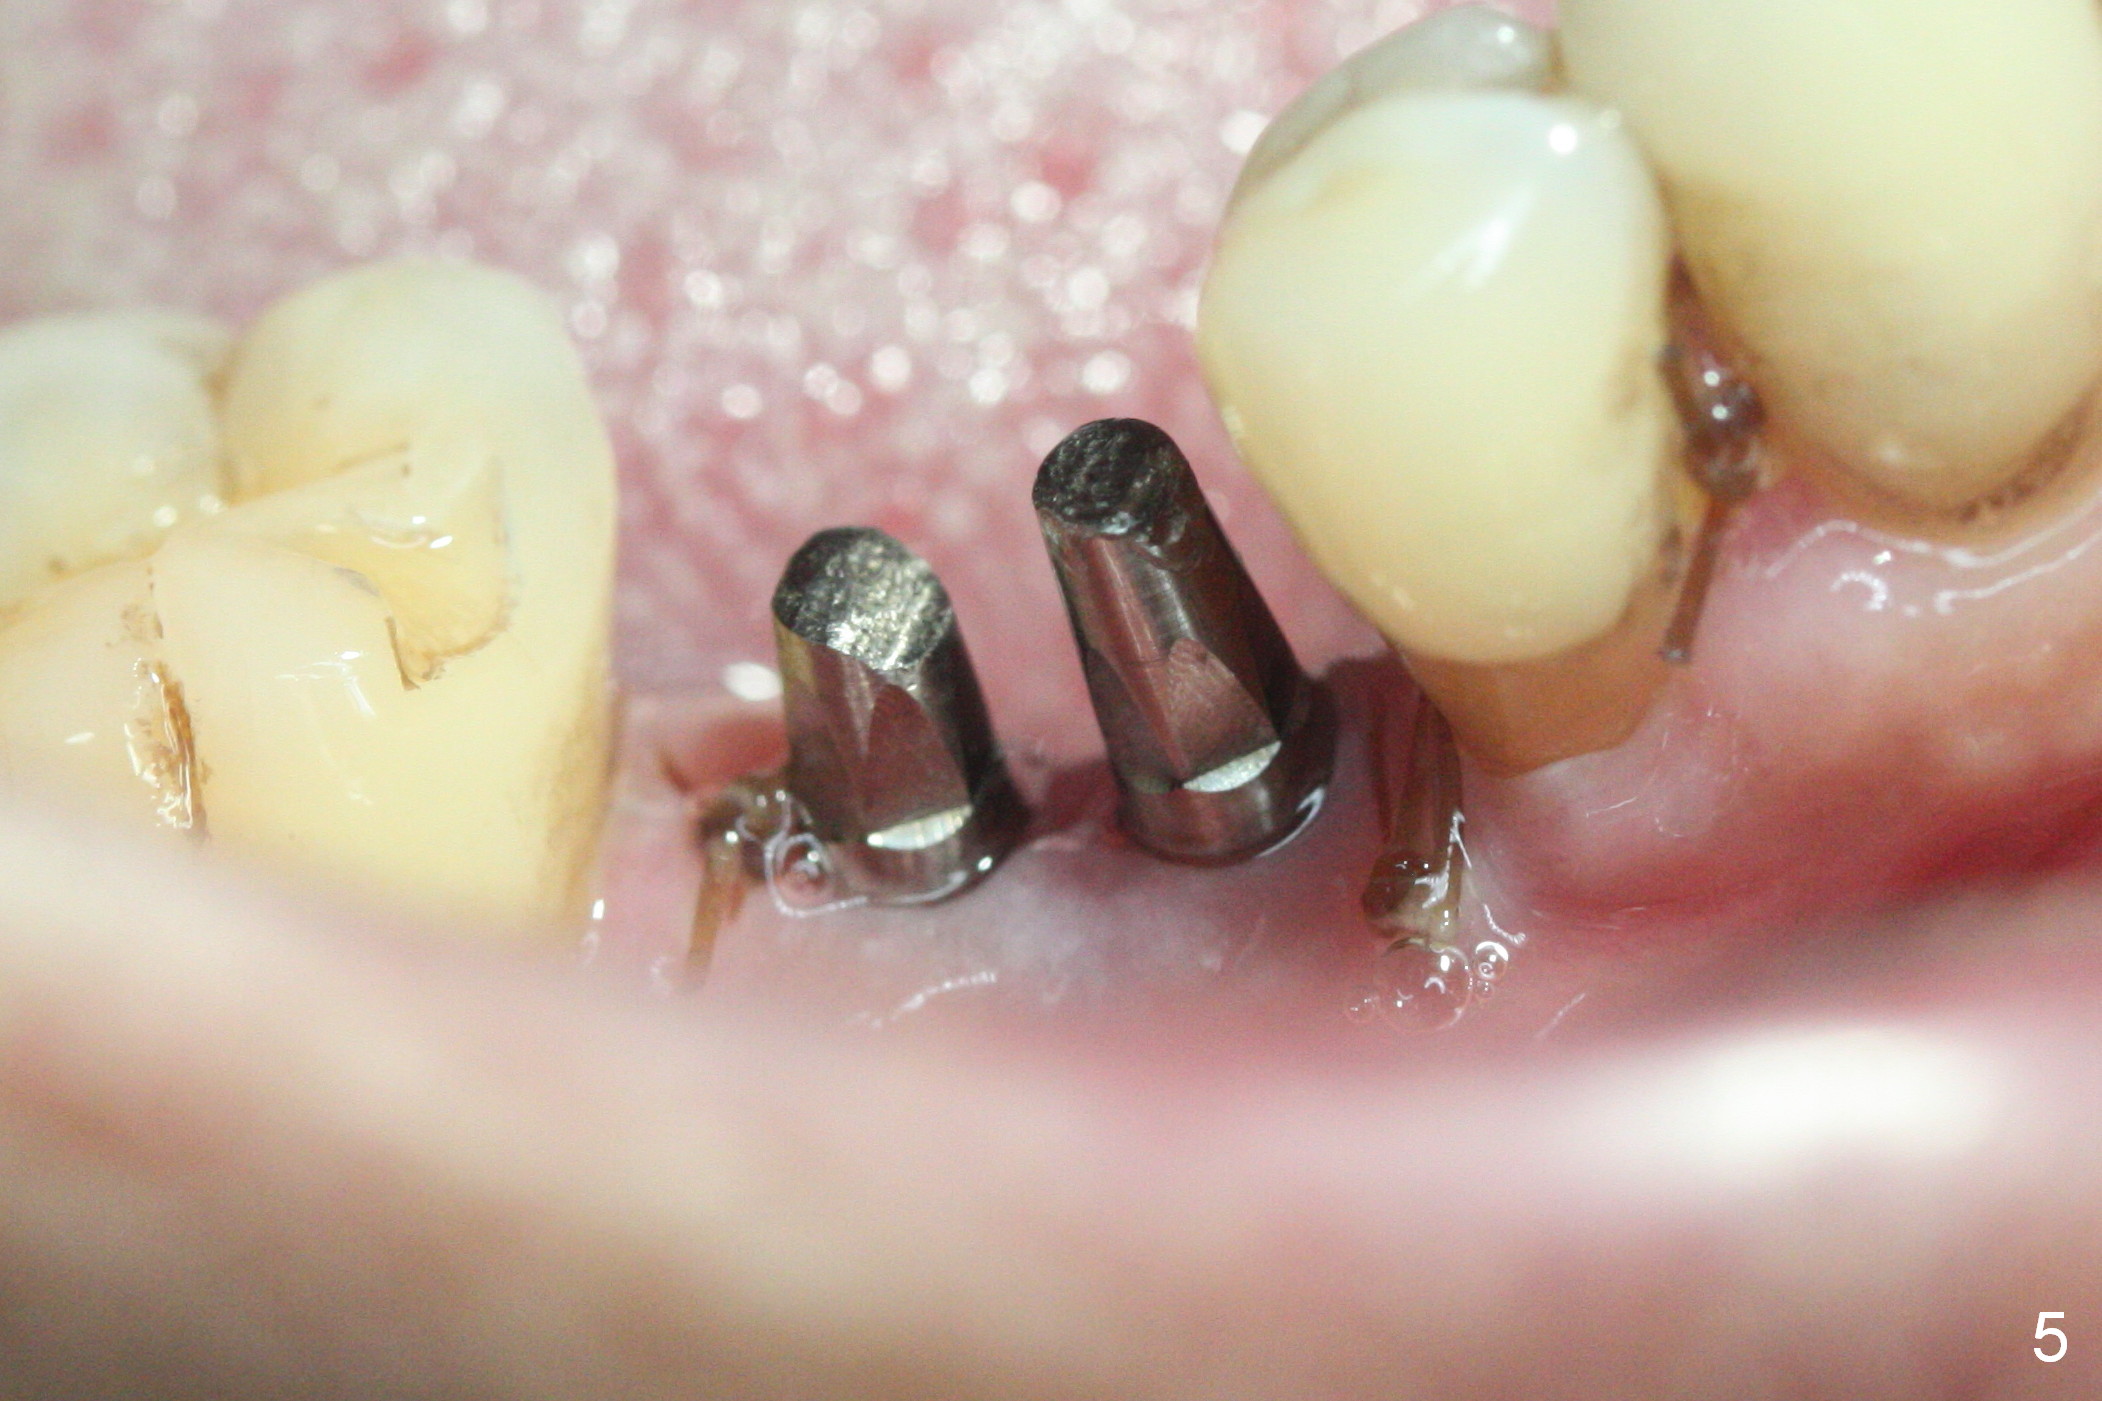

The wide mesiodistal space at #29 is most likely due to congenital missing permanent tooth (i.e., deciduous molar retention before extraction 34 years ago). The patient is now 62 years old. In fact the buccolingual width is not so narrow (Fig.1). After incision, the ridge is approximately 5 mm. Two osteotomies are established with 1.2 mm drill at 8 mm mesially and 1.5 mm one at 10 mm distally (Fig.2). The apparent approximation of the mesial osteotomy to the Mental Loop (red dashed line) is related to X-ray angulation, since there is 1-2 mm separation when two of 2x10(2) mm 1-piece implants are placed (Fig.3,4). Insertion torques of the mesial and distal implants are less than 25 and 15 Ncm, respectively. In fact bone graft is placed around the distolingual root of the tooth #30 after calculus removal (Fig.4 <). Following reduction of the abutments, periodontal dressing is applied locally. The dressing dislodged 13 days postop (Fig.5). A provisional is going to be fabricated 4 weeks postop when the wound heals (Fig.6). No bone loss is observed 4 months postop (Fig.7).